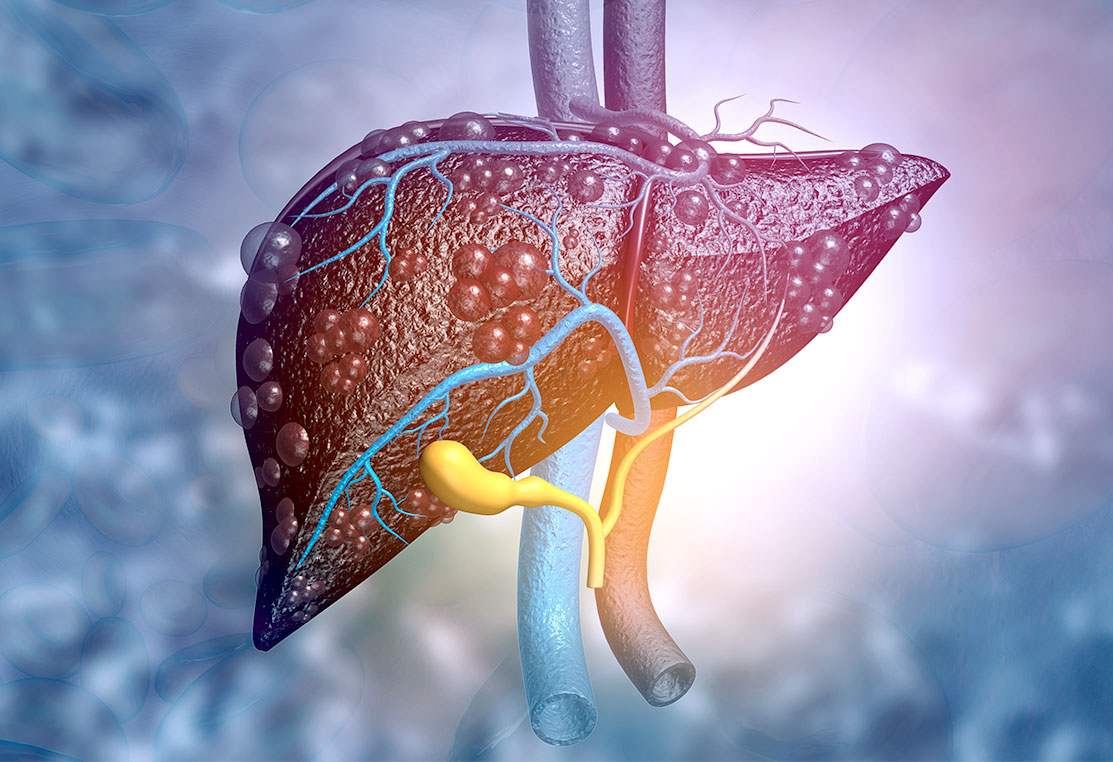

- Increased risk of liver cancer

If a patient has cirrhosis, it means that their liver has reached the stage where it can no longer regenerate.